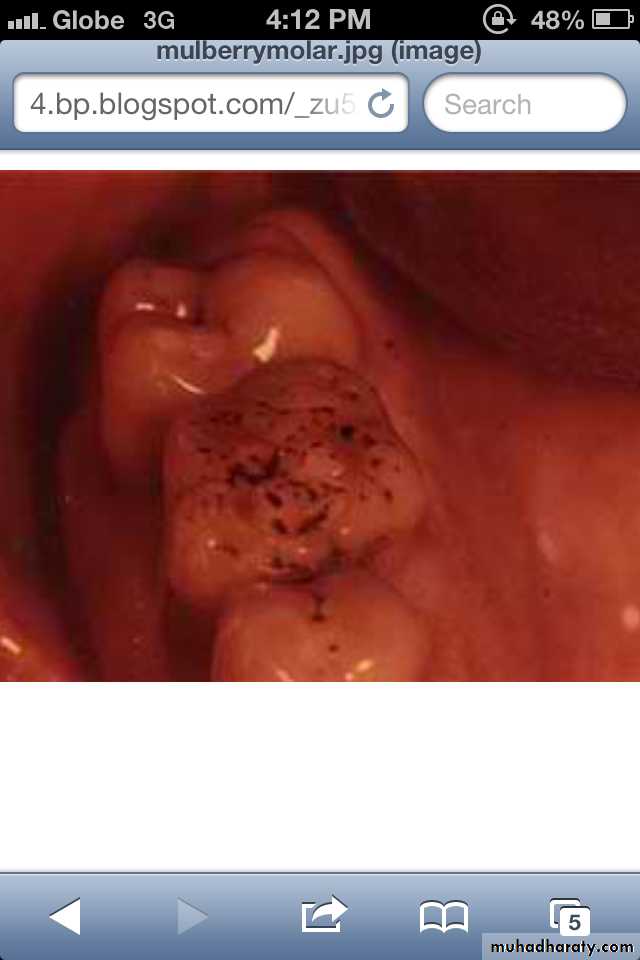

Characterized by multiple rounded rudimentary enamel cusps on permanent 1st molars.

dwarfed molars with cusps covered with globular enamel growths giving the appearance of a mulberry.* Mulberry Molar